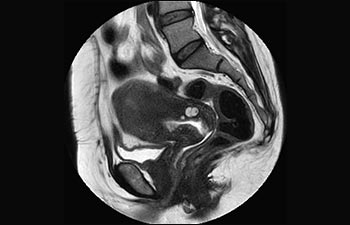

1 In base a uno studio interno in cui si confronta il flusso di lavoro con il sistema RM Achieva. 2 ComforTone sarà disponibile con Prodiva 1.5T a partire da fine 2017. 3 In base a uno studio interno che ha confrontato il flusso di lavoro di una serie di applicazioni su cervello, colonna vertebrale, apparato muscoloscheletrico e corpo con il sistema RM Achieva. 4 Per normale funzionamento si intende una scansione tipica eseguita in condizioni di disponibilità ininterrotta di elettricità, con raffreddamento del magnete e senza interventi di assistenza. 5 A seconda di quanto previsto nel contratto e della disponibilità locale. 6 "Altri" si riferisce a sistemi RM 1.5T da 60 cm per il corpo intero